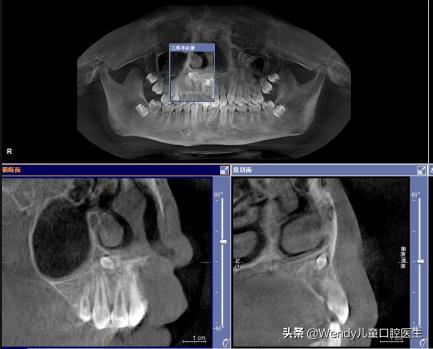

前天小泽妈带着小泽来看牙,乳牙按时掉了可惜新长出的恒牙怎么看都不对劲,形态怪异,一般这种情况首先考虑多生牙,建议拍摄全景片。果不其然,新长出的的确是多生牙,除外还发现颌骨里长了另一颗倒置的多生牙,这颗多生牙斜着挡在恒牙的上方,对恒牙萌出一定有影响,建议拔除。

多生牙的确诊以及治疗拔除都需要在X线片下才能明确,常见的X线片有根尖片,全口曲面断层片和CBCT。

正因为多生牙多发生在换牙期,所以对于5-7岁的儿童进行一次X线片的拍摄是非常有必要的,便于早发现早诊断早处理。